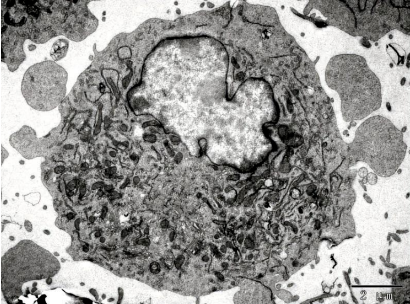

圖片來源:《腦腫瘤與神經(jīng)組織電鏡圖譜》編著 孫異臨 人民衛(wèi)生出版社